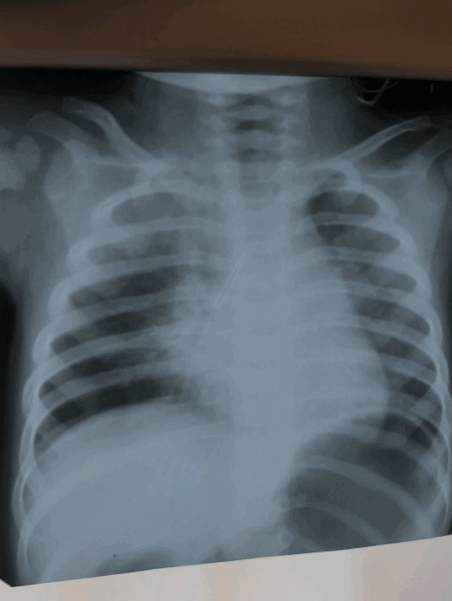

Пациентка Дарья К. 17.01.2020. рождения поступила в нашу клинику 26.01.2021, из анамнеза: около двух недель болеет пневмонией, по поводу чего получала лечение амбулаторно по месту жительства, где и выполнили R-графию ОГК, на которой выявлено инородное тело, предположительно металлического характера, предположительно в правом главном бронхе: